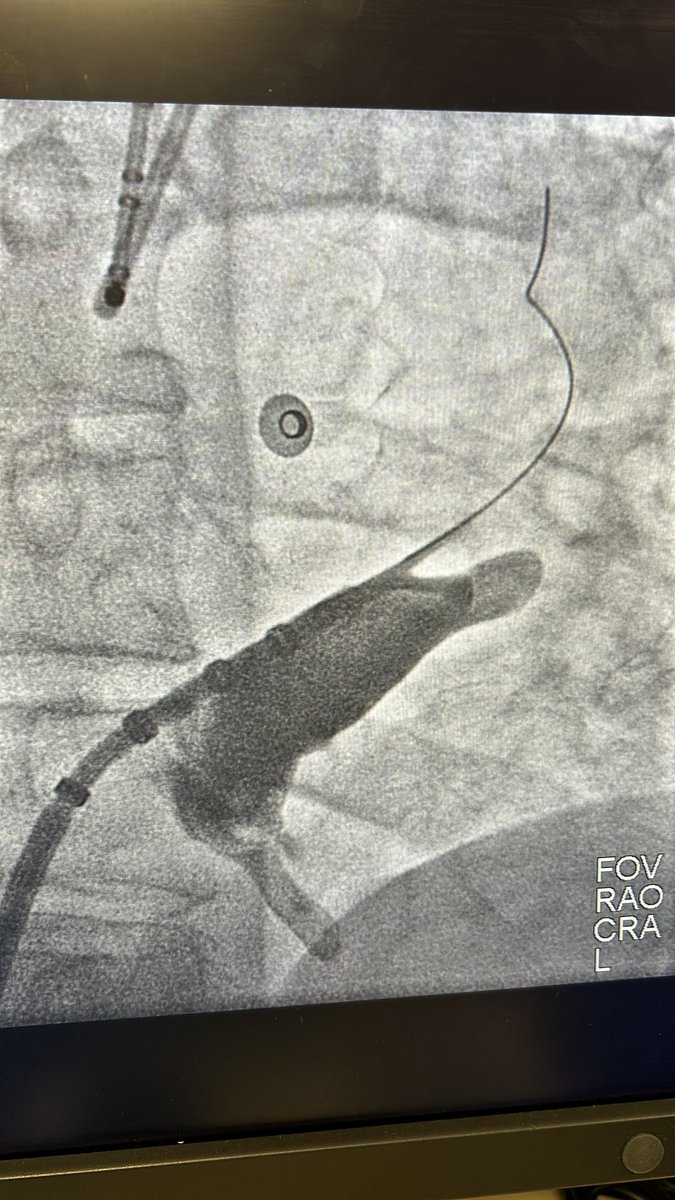

More evidence mounting that lines of block during baseline rhythm are indeed fixed isthmus boundaries for VT. 👏🏻@Davilandre @BidmcCvi

pubmed.ncbi.nlm.nih.gov/38819346/ VT ablation without the need for VT induction and the use of activation map to better understand the substrate.